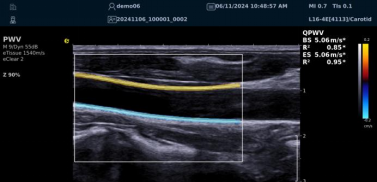

image.png

? 可进行动脉壁运动速度 - 时间彩色成像,直接测量单点脉搏波传导速度及相关参数(如 BSES 时的速度及标准差)。

? 能在血管内中膜增厚前的内皮功能不全阶段检测异常,对早期动脉硬化评估极具临床价值。

? 操作简单直接,无需附加设备,影响因素少,检测快速、重复性和稳定性高。